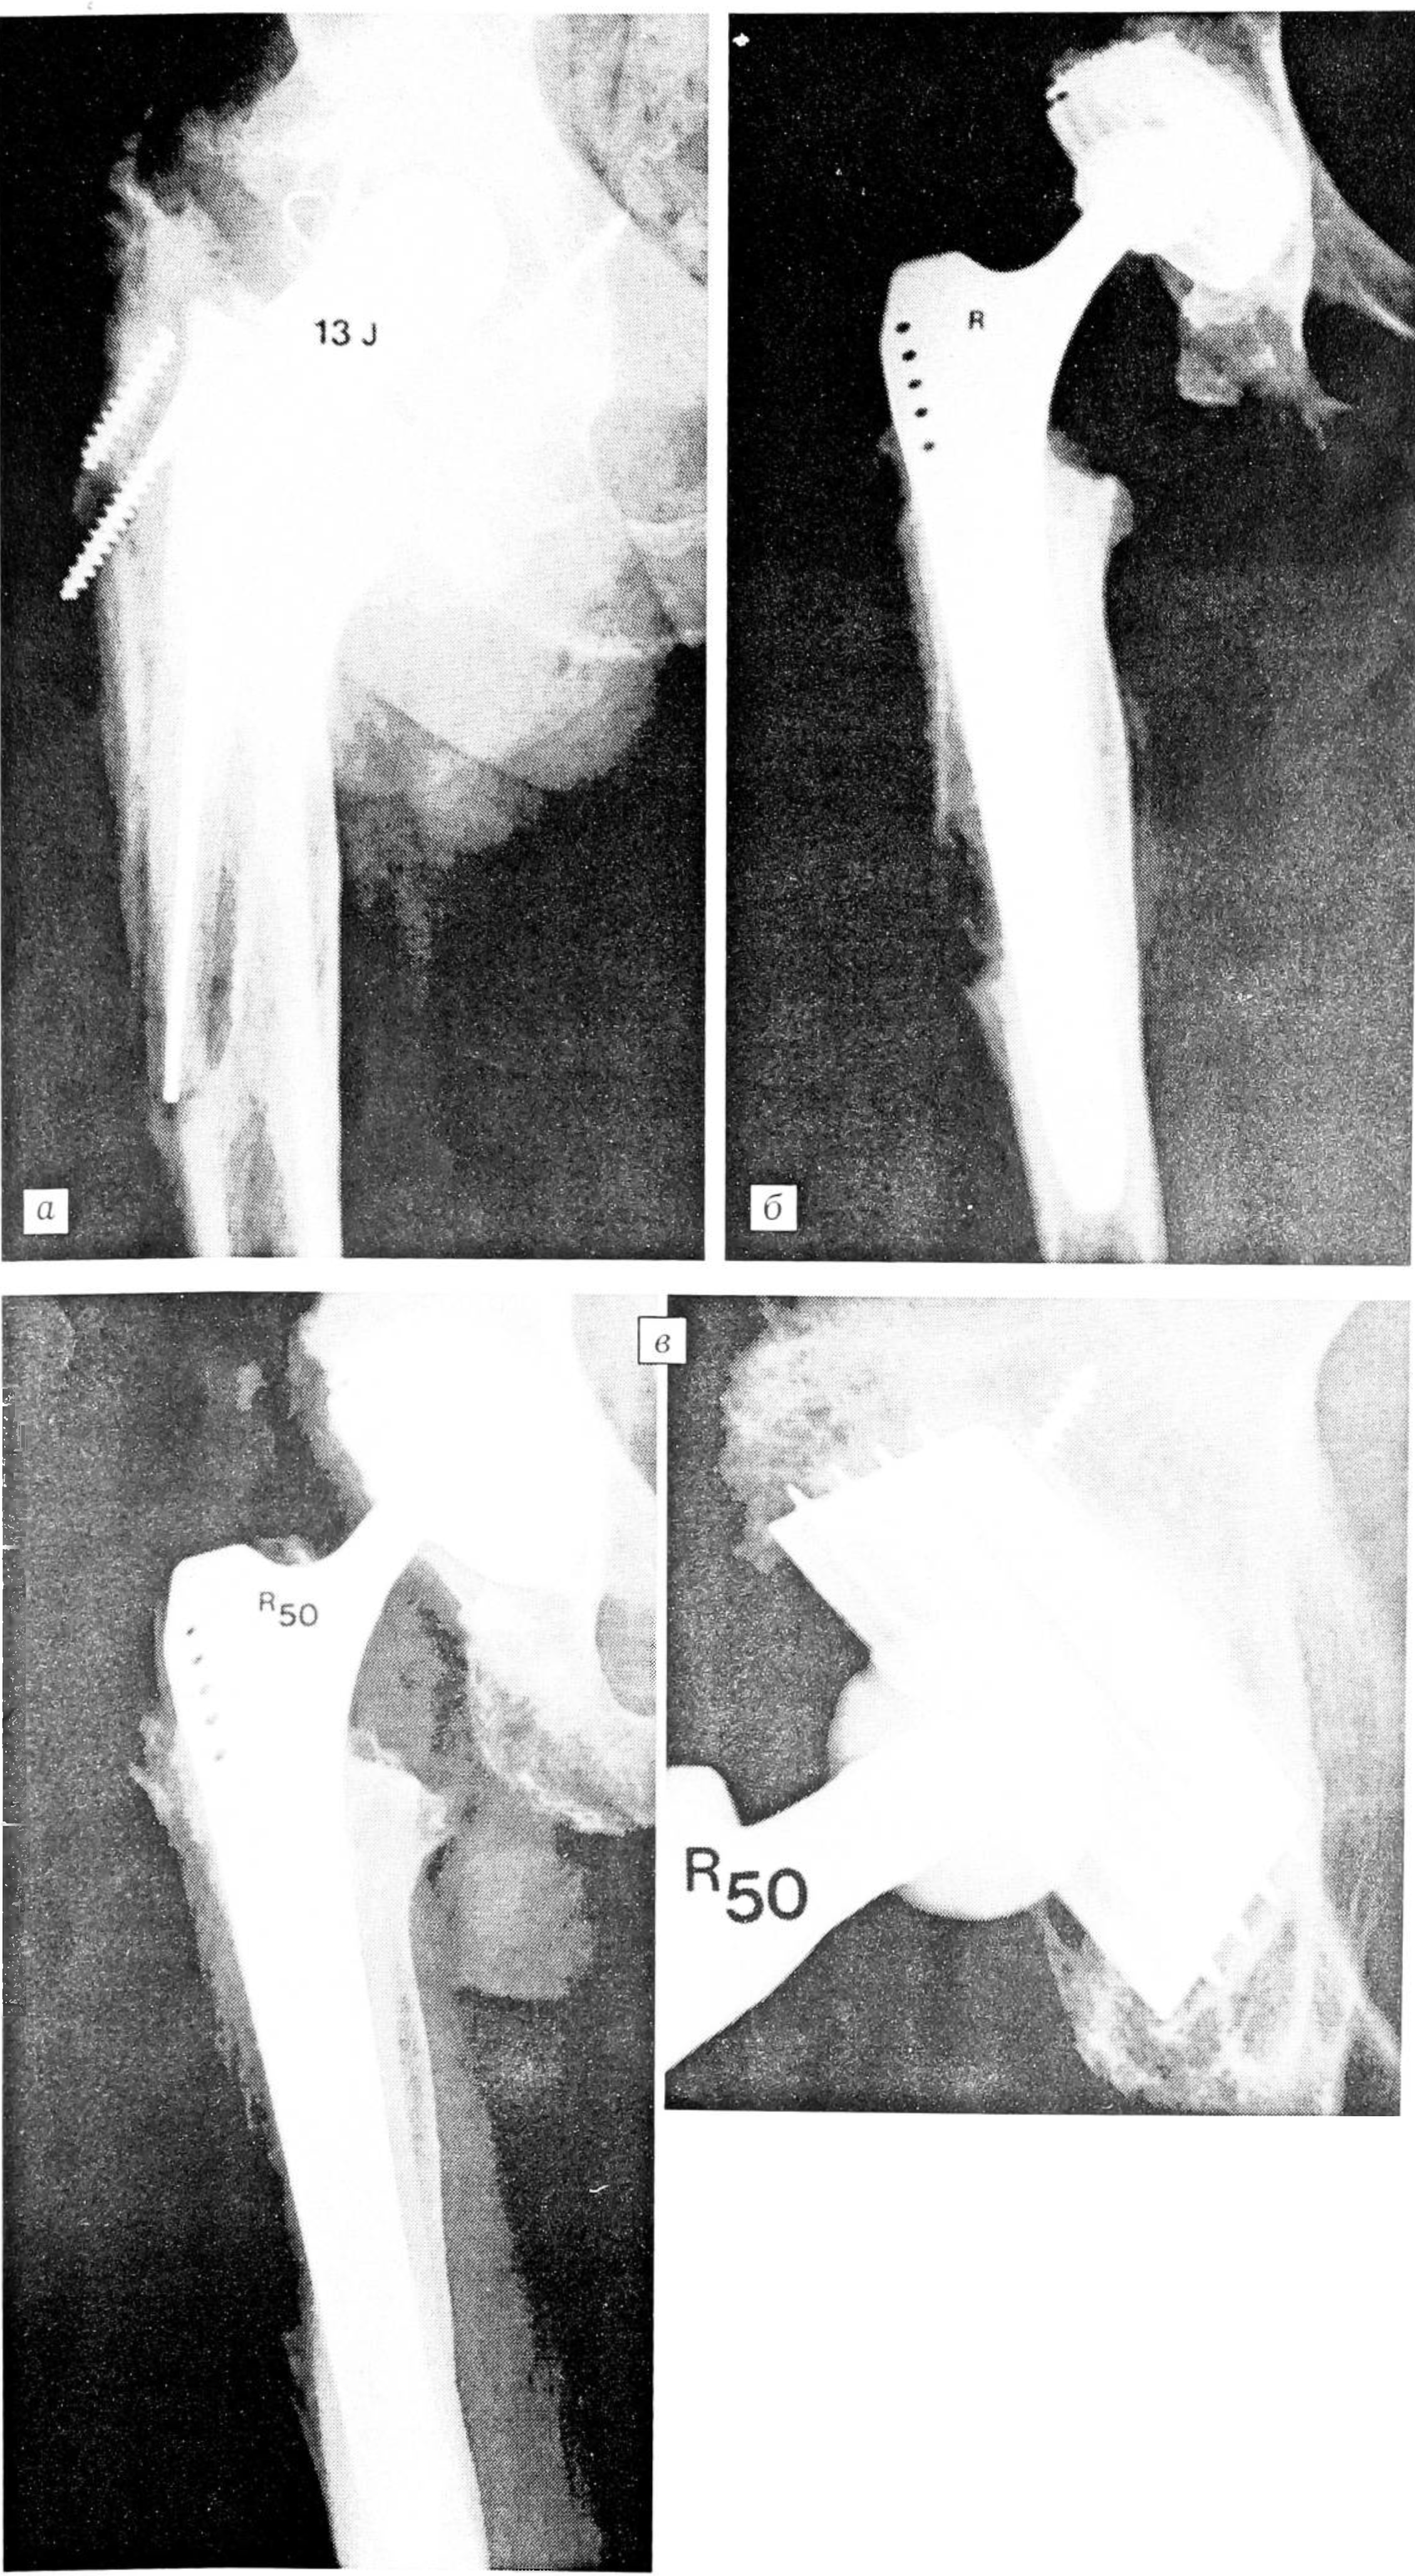

Рис. 3.

а — через 13 лет после первичного тотального бесцементного эндопротезирования тазобедренного сустава: выраженный кортикальный дефект в зоне дистальной трети ножки;

б — непосредственно после повторного тотального бесцементного эндопротезирования (чашка Bicon Zweymuller, ножка SLR-Plus);

в — через 45 мес после повторного эндопротезирования: хорошая костная интеграция вокруг компонентов эндопротеза.

Engelbrecht 4. При таких больших разрушениях проксимального конца бедра, когда дефект достигает в длину более 15 см, ножка SLR не может быть надежно зафиксирована. Поэтому в подобных случаях приходится использовать другие ревизионные ножки. Мы применяем ножку Vagner, которая может иметь длину до 305 мм и обычно имплантируется в бесцементном варианте. В очень редких случаях требуется тотальное замещение бедренной кости.